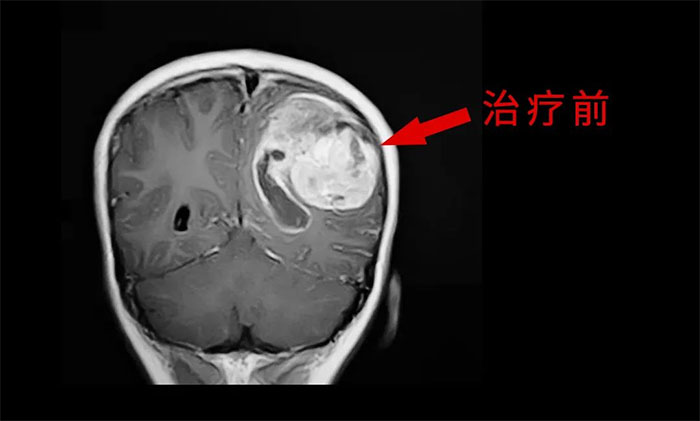

目前,腦膠質(zhì)瘤的治療方面,倡導(dǎo)MDT多學(xué)科診治,神經(jīng)外科、影像科、放射治療科、腫瘤科、病理科和康復(fù)科等多學(xué)科合作,遵循循證醫(yī)學(xué)原則,優(yōu)化和規(guī)范治療方案,采取個體化綜合治療,以期達(dá)到最大治療效益,盡可能延長患者的無進(jìn)展生存期(PFS) 和總生存期(OS),提高生存質(zhì)量。

外科手術(shù)往往是膠質(zhì)瘤治療的第一步。手術(shù)原則是在最大范圍安全切除(maximal safe resection)腫瘤的同時,保護(hù)神經(jīng)功能區(qū)。以解除占位征象和緩解顱內(nèi)高壓癥狀;解除或緩解因腦膠質(zhì)瘤引發(fā)的相關(guān)癥狀;獲得病理組織和分子病理,明確診斷;降低腫瘤負(fù)荷,為后續(xù)綜合治療提供條件。

放、化療等亦是不可或缺的重要治療手段,高級別膠質(zhì)瘤術(shù)后選擇標(biāo)準(zhǔn)同步放、化療可以取得顯著的生存獲益。

于耀宇主任特別指出,隨著腦血管介入技術(shù)快速發(fā)展,腦膠質(zhì)瘤術(shù)后超選介入化療聯(lián)合同步放療的效用正逐漸為大家所認(rèn)識。超選介入化療,是利用微導(dǎo)管技術(shù)直接將藥物通過供血動脈,灌注到顱內(nèi)腫瘤組織區(qū)域,避免了傳統(tǒng)口服或靜脈注射藥物,要經(jīng)過全身代謝后才能到達(dá)腫瘤區(qū)域?蓽p輕全身毒性反應(yīng),延長化療藥在腫瘤內(nèi)的滯留時間,更好地殺傷腫瘤細(xì)胞。

最后,于耀宇主任表示,膠質(zhì)瘤固然兇險,但我們應(yīng)當(dāng)正確認(rèn)識疾病,不盲目悲觀,更不應(yīng)輕易放棄治療。隨著醫(yī)療技術(shù)水平和治療手段的不斷提高,膠質(zhì)瘤患者在接受規(guī)范的治療后,延長生存期已成為可能,大可不必“談瘤色變”。